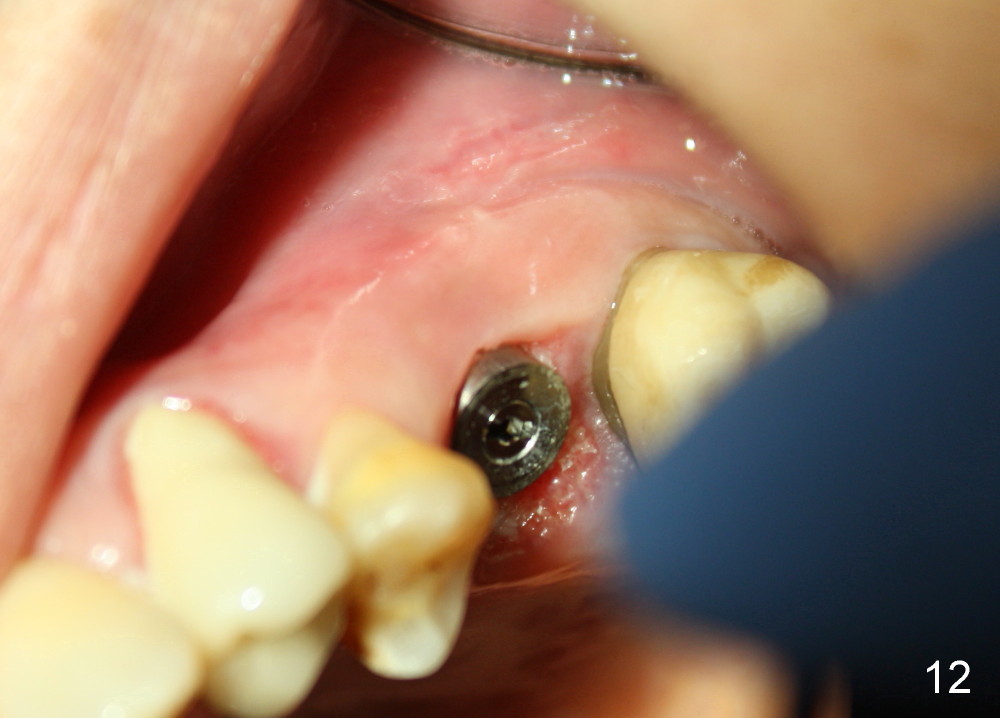

The 2nd perio dressing lasts for another two weeks. When it is removed in clinic, the wound heals; the implant is shown placed slightly buccally (Fig.11, occlusal mirror image). Buccal view shows that the fistula dissolves (Fig.12).